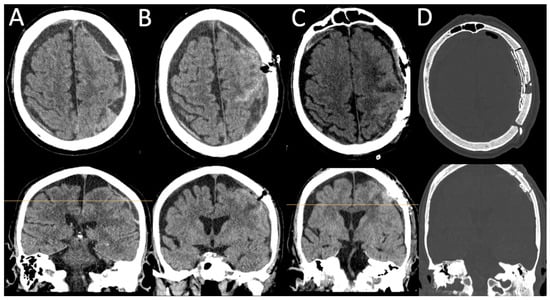

After the patient showed no clinical improvement, we identified an indication for revision surgery by means of craniotomy and hematoma evacuation, which was performed using the herein-introduced endless-loop craniotomy technique. Details of the surgical steps are displayed in the next section. Because of the vulnerable cortex and an already-present postoperative hemorrhage, we chose a non-watertight dura closure, and an epidural Jackson-Pratt drain was left for 2 days (Figure 1C,D). Figure 2 shows an illustration of the two different surgical techniques in a sagittal CT scout: burr-hole (A) and endless-loop craniotomy (B). The detailed operative steps for craniotomy, dura opening, and drain management are shown in Figure 3 and Figure 4. The operation was performed as planned without intraoperative complications.

Figure 2. (A): Sagittal X-ray after burr-hole evacuation of bilateral chronic subdural hematomas. (B): X-ray after revision surgery with endless-loop craniotomy. Note the in situ Jackson-Pratt drain directed posteriorly.